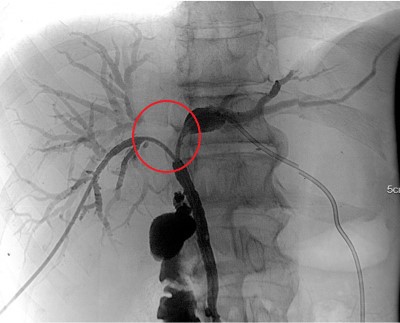

Материалы и методы. С 2017-го по 2021 г. в ФГБУ «РНЦРХТ им. академика А.М. Гранова» в протокол лечения нерезектабельной опухоли Клацкина с последующей трансплантацией печени было включено 6 пациентов. Неоадъювантное лечение включало эндобилиарную фотодинамическую терапию, регионарную и системную химиотерапию. Каждый метод применялся минимум трижды в течение четырех-пяти месяцев с радиологической оценкой и определением уровня Са19-9. Пациенты вносились в лист ожидания при снижении онкомаркера, отсутствии радиологических признаков прогрессии заболевания и без острого холангита. Реципиентам выполнялась лапароскопическая ревизия брюшной полости на предмет канцероматоза и оценка лимфоузлов печеночнодвенадцатиперстной связки со срочным морфологическим исследованием. При отсутствии внепеченочного распространения производилась трансплантация печени по классической методике с паракавальной, парааортальной и гепатодуоденальной лимфодиссекцией, билиодигестивным анастомозом на отключенной по Ру петле тонкой кишки. Операция выполнена трем пациентам, все из них – мужчины. Возраст колебался от 40 до 55 лет (средний – 48). Среднее время от начала лечения до трансплантации составило 9,3 месяца (от 6 до 14). Средний уровень Са19-9 на момент выполнения вмешательства составил 81,3 МЕ/мл (от 8 до 212).

Результаты. У трех пациентов, несмотря на лечение, отмечен рост уровня Са19-9 более чем в два раза в среднем за четыре месяца. У двух из них выявлена прогрессия заболевания согласно данным компьютерной томографии по RECIST. У одного пациента выявлен канцероматоз при диагностической лапароскопии. У трех пациентов Са19-9 снизился более чем в четыре раза. У двух из этих пациентов радиологически подтверждена стабилизация заболевания, у одного – частичный ответ. Один пациент умер через три года после трансплантации от сепсиса в исходе вторичного билиарного цирроза и билиарных абсцессов без признаков прогрессирования. Два пациента живы по настоящее время на протяжении 6 и 21 месяцев без признаков прогрессирования опухоли.